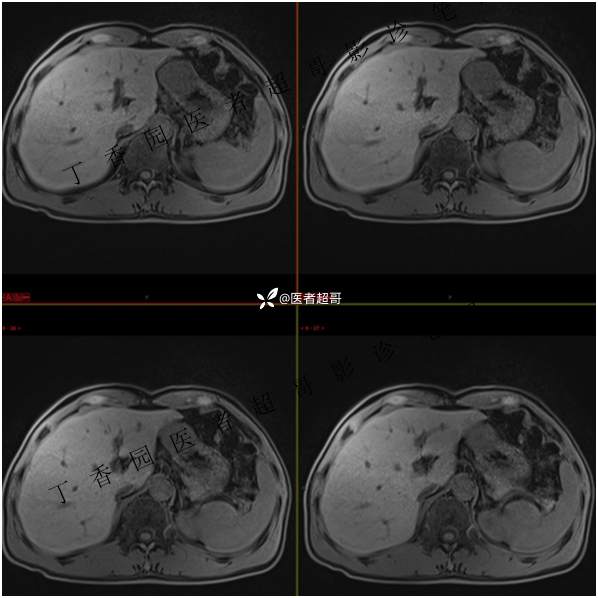

肝胃间隙肿瘤,间质瘤?平滑肌瘤?还是鞘瘤?有结果,请分析!

现病史:患者于3天前查体行肝胆脾胰肾彩超示肝内实性占位,无恶心、呕吐,无发热、寒战,无腹胀、腹泻,进一步于医院行上腹部CT增强示:肝胃交界处肿块。未行特殊治疗。今患者为求进一步治疗,来我院就诊,门诊以“肝占位性病变”收入院。患者自发病以来,神志清,精神可,饮食睡眠可,二便可,体重近期未见明显变化。